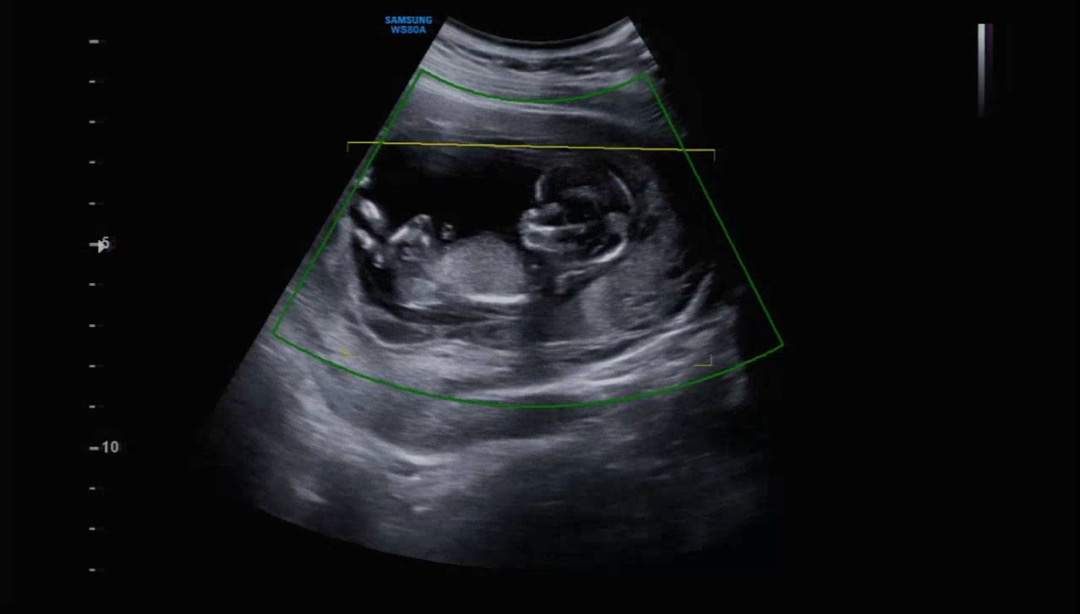

13주차 1차기형아검사

엊그제 1차 기형아검사 무사히 마치구왔어요! 3주만에 아가보니 젤리곰에서 사람이되었네요ㅠㅠ 띠용이가 너무 활발하게 잘 움직여줘서 투명대 검사도 금방 하고, 이시기에는 손가락 발가락 보기가 힘들다던데 띠용이가 너무 씩씩하게 손가락도 잘 보여줘서 너무 기특하네요 ㅎㅎ 초음파내내 다리를 가만두지못하고 활발하게 움직이더니 저렇게 다리 꼬고 있는게 너무 귀엽지 않나요 ㅋㅋㅋㅋㅋ❤️❤️ 지금은 정확하진 않다지만 살짝 성별 힌트를 주시더라구요 70프로 아들인거같다고 하시는데 70프로면.. 반전이있을까요?ㅎㅎ 아들이던 딸이던 그저 넘 좋으네요 ᰔ 저희지역은 눈이 많이왔는데 베동맘들도 안전하고 좋은 하루 보내세요 :)